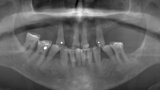

Fig. 5. Prótesis Híbrida inmediata y radiografía control con 6 años post-operatorio